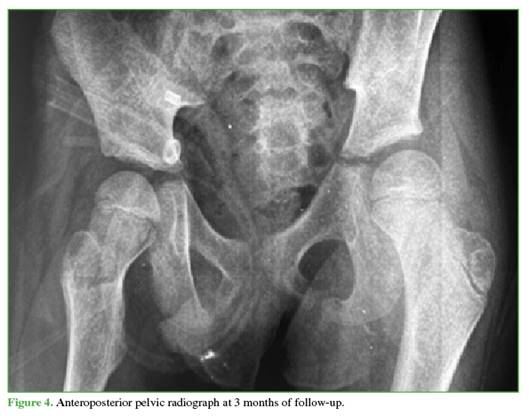

Follow-up radiographs at 3 (Figure 4) and 6 months (Figure 5) showed no evidence of AVN, and other musculo-skeletal complications associated with traumatic dislocation were also ruled out.

Reported complications include coxa magna, sciatic nerve palsy, paresthesias, and AVN of the femoral head.10 In patients under 18 years of age, the incidence after isolated dislocation ranges from 3% to 15%,17 and is higher if reduction is delayed.18 Therefore, imaging follow-up is essential. Although there is no consensus on ideal timing, in this case, check-ups were performed at 3 and 6 months, and no radiographic evidence of AVN was detected.

Follow-up radiographs showed no signs suggestive of AVN (sclerosis, collapse, cysts, joint-space narrowing, etc.).22 These findings may take 2 to 6 months to become visible on radiographs,20 so the follow-up schedule was appropriate.